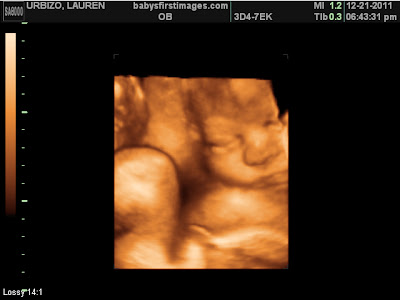

Copelyn and I are doing well! We got to see her this past week and she is so cute! She looks a lot like her daddy even though I don't want to admit it since I am the one who has been carrying her for 9 months!! She has the cutest cheeks and I can't wait to kiss them! We still have been exercising daily but sweet girl has made it kind of difficult. She still pushes as hard as she can against me and I have tried to tell her that she is pushing on my organs & it hurts!!...But she doesn't listen! I fall asleep at about 9pm every night due to the fact she gets me up now at least 5 times a night to pee! I guess she is breaking me in for motherhood which is just fine because then I will be used to it by the time she gets here in 6 weeks. My dilated vein gets bigger and bigger by the day it seems. I have found the longer I stand still without walking makes it worse but as long as I am moving it doesn't bother me. I think she has a thing for my right side because that is where she puts all her pressure. At our ultrasound this past week it looks as though she has turned breech again. ugh! So prayers would be appreciated that she turns head down before she decides to make her arrival. I think she probably just doesn't want to be upside down for that long so she is waiting to turn back around. I don't think I would like to hang upside down for 6 weeks either!